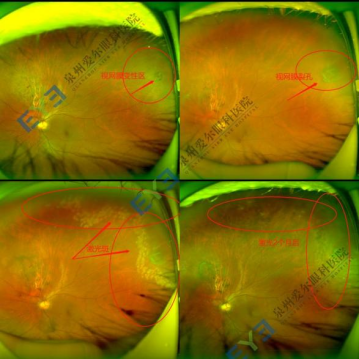

(视网膜裂孔激光治疗前后对比图)